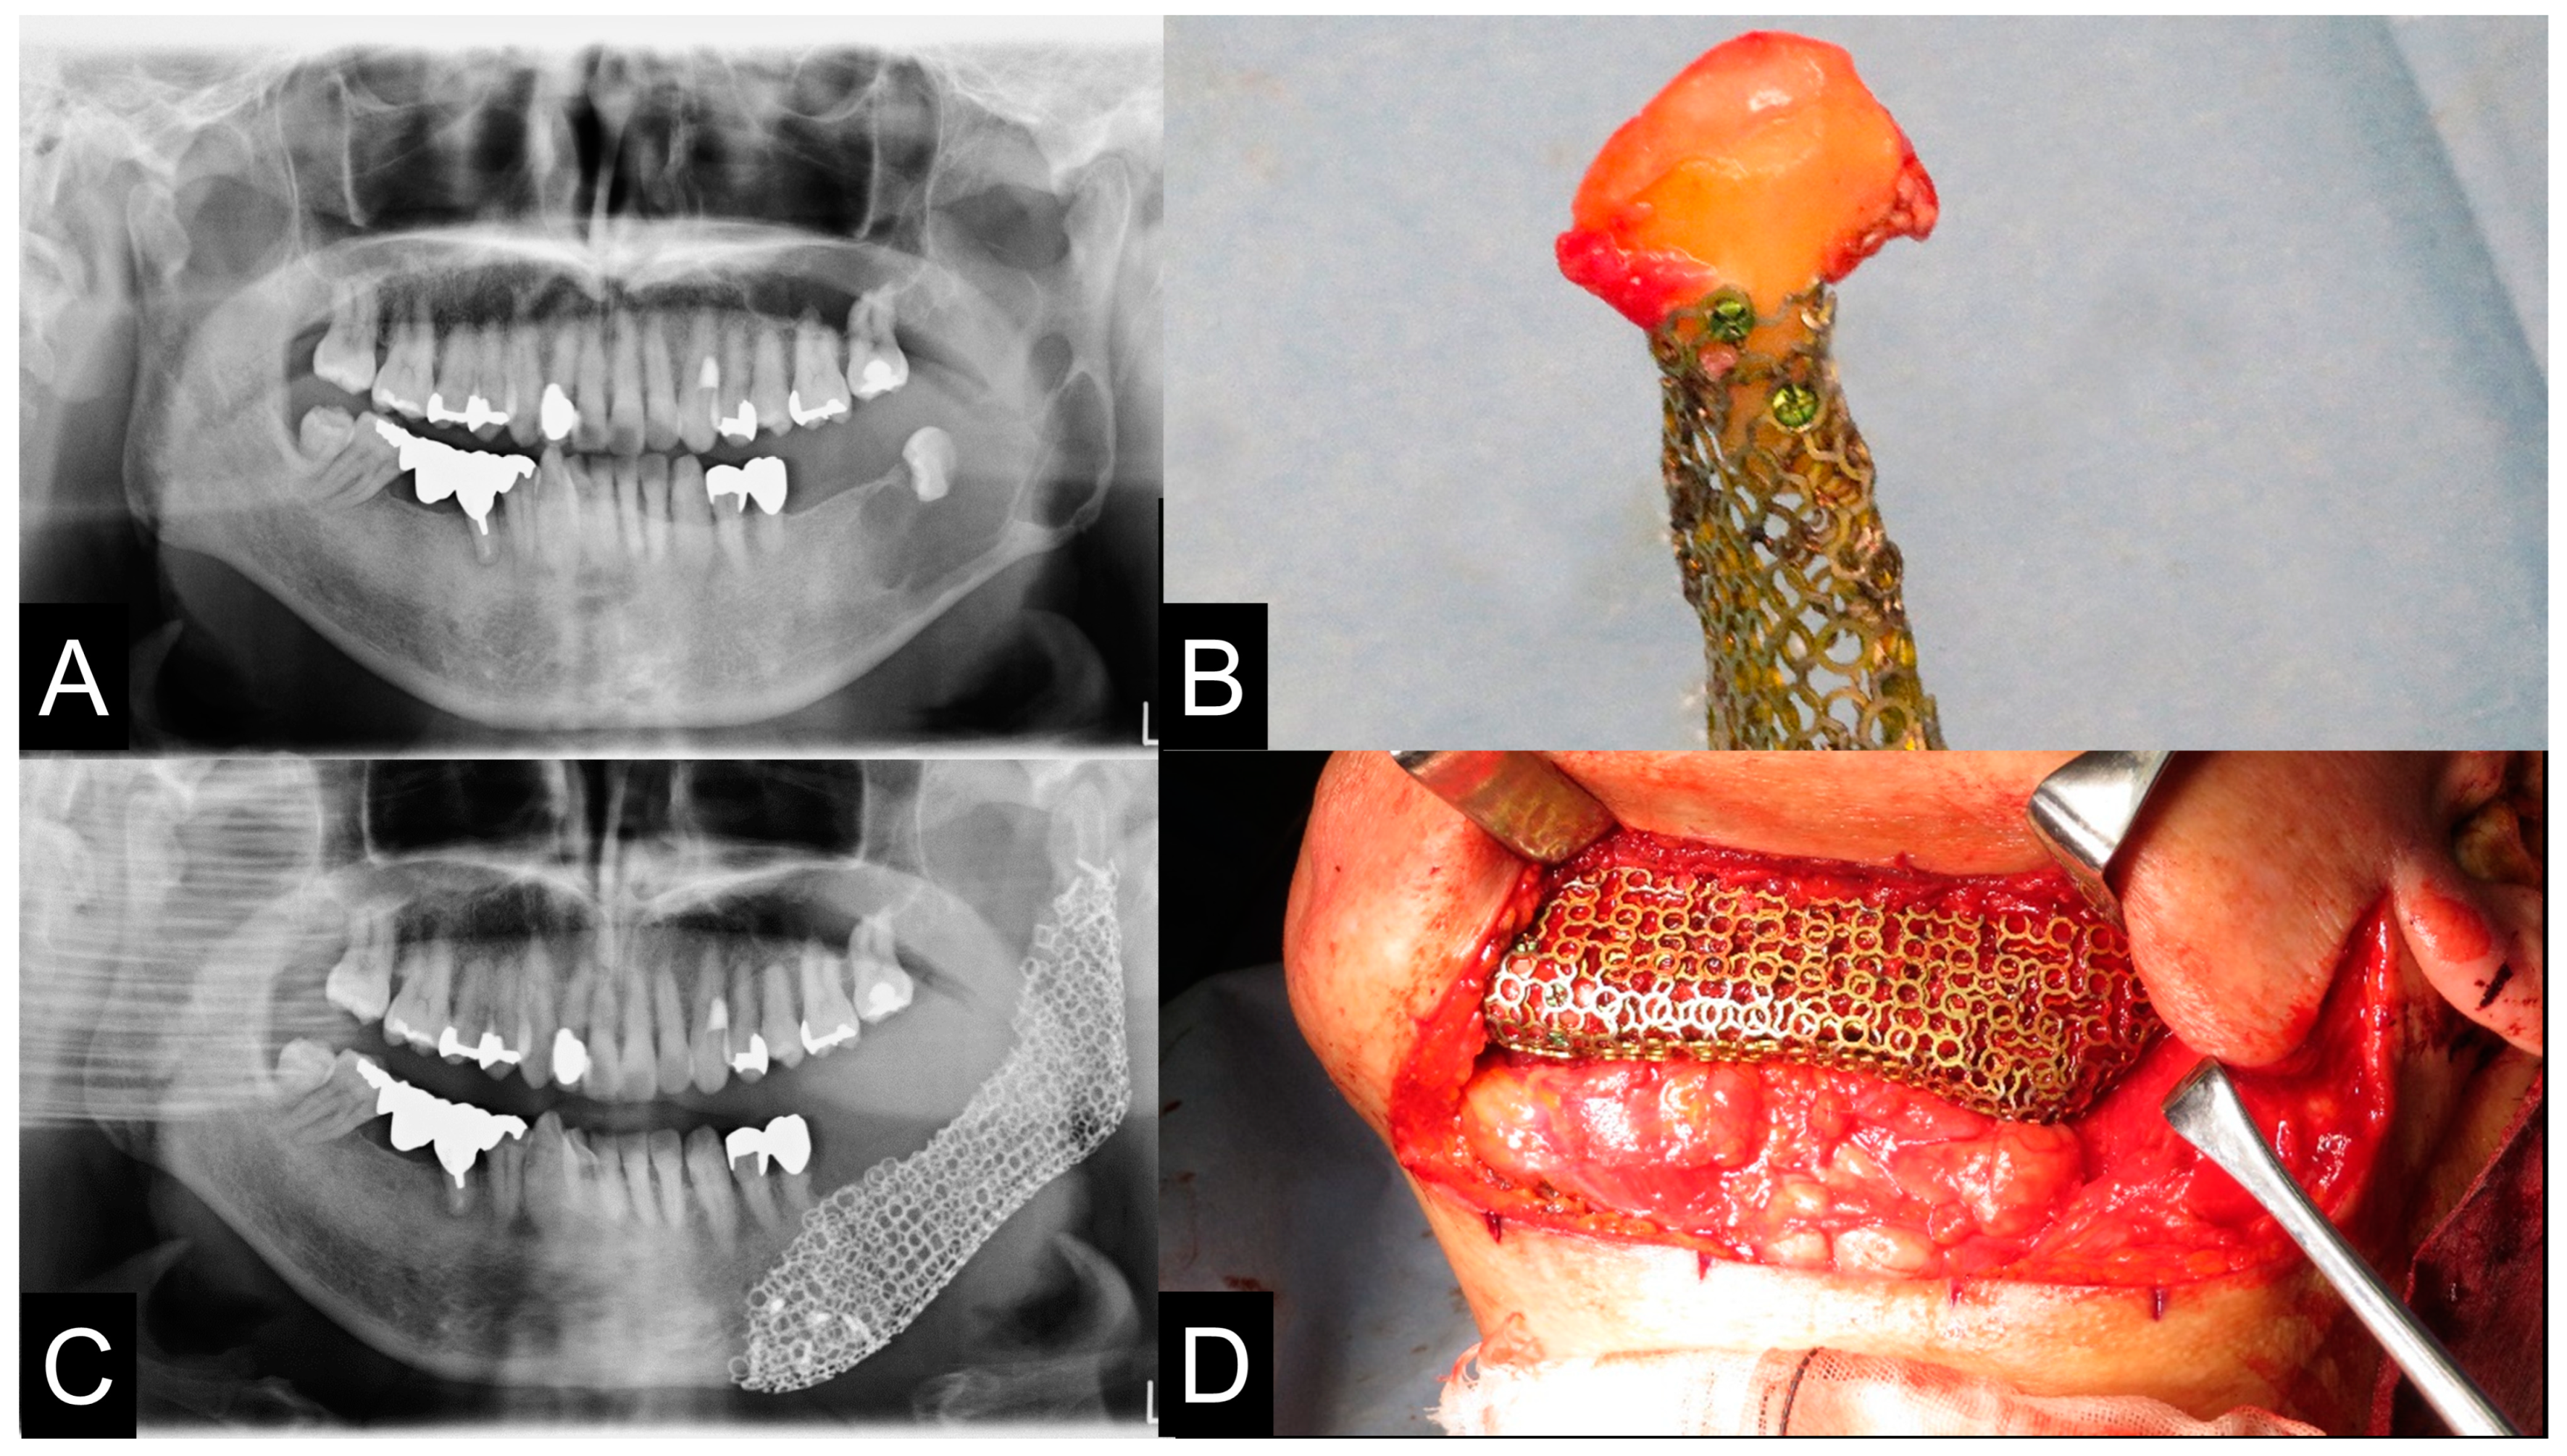

| Case | Virtual Reconstruction Technique | Preoperative Simulation of PCBM Amount | The Reality of PCBM Quantity | Preoperative Length (mm) | Postoperative Length (mm) | A Preoperative Sum of the Condylar Axial Angles (Degree) | A Postoperative Sum of the Condylar Axial Angles (Degree) |

|---|---|---|---|---|---|---|---|

| 1 | Level 1 | 2.2 cc | 6.4 cc | 26.7 mm | 25.8 mm | 126° | 127° |

| 2 | Level 2 | 11.3 cc | 20 cc | 45.4 mm | 50.4 mm | 141° | 151° |

| 3 | Level 2 | 11.9 cc | 23 cc | 36.0 mm | 36.0 mm | 150° | 151° |

| 4 | Level 1 | 6.51 cc | 10 cc | 37.7 mm | 37.7 mm | 148° | 147° |

| 5 | Level 2 | 11.3 cc | 17 cc | 46.0 mm | 53.5 mm | 153° | 142° |

| 6 | Level 1 | 14.2 cc | 30 cc | 63.3 mm | 63.3 mm | 143° | 143° |

| 7 | Level 1 | 8.2 cc | 10 cc | 54.6 mm | 54.6 mm | 131° | 131° |

| 8 | Level 1 | 16.8 cc | 17 cc | 69.0 mm | 69.0 mm | 129° | 128° |

| 9 | Level 2 | 20 cc | 40 cc | 63.4 mm | 65.7 mm | 106° | 132° |

| 10 | Level 2 | 19.3 cc | 40 cc | 70.7 mm | 77.7 mm | 129° | 136° |

| 11 | Level 2 | 10 cc | 15 cc | 56.3 mm | 53.1 mm | 136° | 140° |

| 12 | Level 1 | 8 cc | 14 cc | 40.6 mm | 40.6 mm | 149° | 149° |

| 13 | Level 2 | 10 cc | 19 cc | 35.3 mm | 42.4 mm | 150° | 145° |

| 14 | Level 3 | 10.4 cc | 20 cc | 56.3 mm | 59.6 mm | 172° | 161° |

| 15 | Level 3 | 10.6 cc | 24 cc | 54.5 mm | 61.0 mm | 197° | 197° |

| 16 | Level 2 | 9.6 cc | 21 cc | 30.8 mm | 36.0 mm | 164° | 160° |

| 17 | Level 1 | 5.1 cc | 10 cc | 44.5 mm | 44.5 mm | 122° | 122° |

| 18 | Level 2 | 17.7 cc | 32 cc | 54.5 mm | 72.5 mm | 137° | 140° |